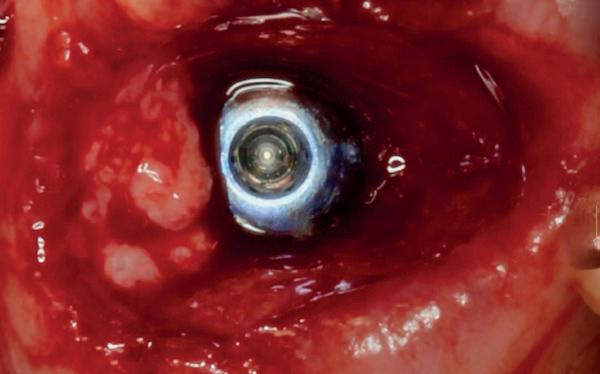

2. Beoordeling van zacht weefsel en botcontour.

Na het klinische onderzoek volgde het röntgenologisch traject. De CBCT liet precies zien wat we al vreesden: een front waarin het bot onregelmatig was, duidelijke radiolucenties rond de pijlers en een infectiegebied dat zich onder vrijwel de gehele brug had verspreid. Tegelijkertijd was er ook potentie. Net voldoende botstructuur om immediate implantaatplaatsing te overwegen, mits alles perfect gepland zou worden.